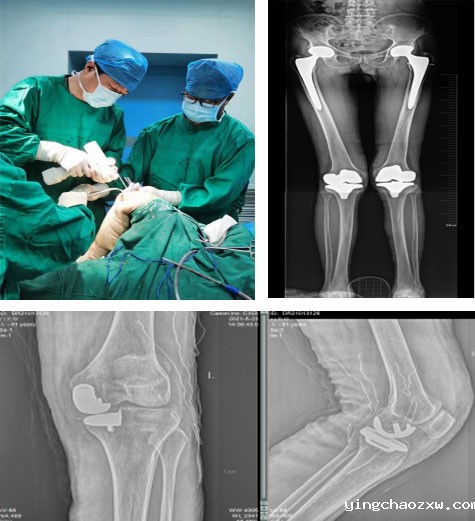

主要收治骨外科、神经外科、创伤外科、烧伤外科、血管外科患者,先后开展人工髋关节置换术、膝关节置换术、人工肩关节置换术、人工膝关节单髁置换术、髋关节感染病灶清除Spaecr植入术、下肢深静脉栓塞滤器植入术、下肢深静脉栓塞经皮导管溶栓术、膝关节关节镜下清理、半月板缝合、交叉韧带重建术、脊柱内镜下椎间盘摘除术、颈腰椎间盘突出椎管减压融合术,腰椎管狭窄、腰椎滑脱椎管减压术、融合术,脊柱骨折内固定术、椎体成形术(PKP、PVP)等多项现代医疗技术及骨盆骨折、四肢创伤骨折、脱位等手术。近年来,外二科各项现代医疗技术不断涌现,先后开展了外周血管介入手术、椎间孔镜下椎间盘摘除术、(MIS-TLIF)微创椎间融合术治疗腰椎间盘突出症、神经介入手术、脑出血微创治疗、脑膜瘤切除术等新技术。

髋、膝关节置换术